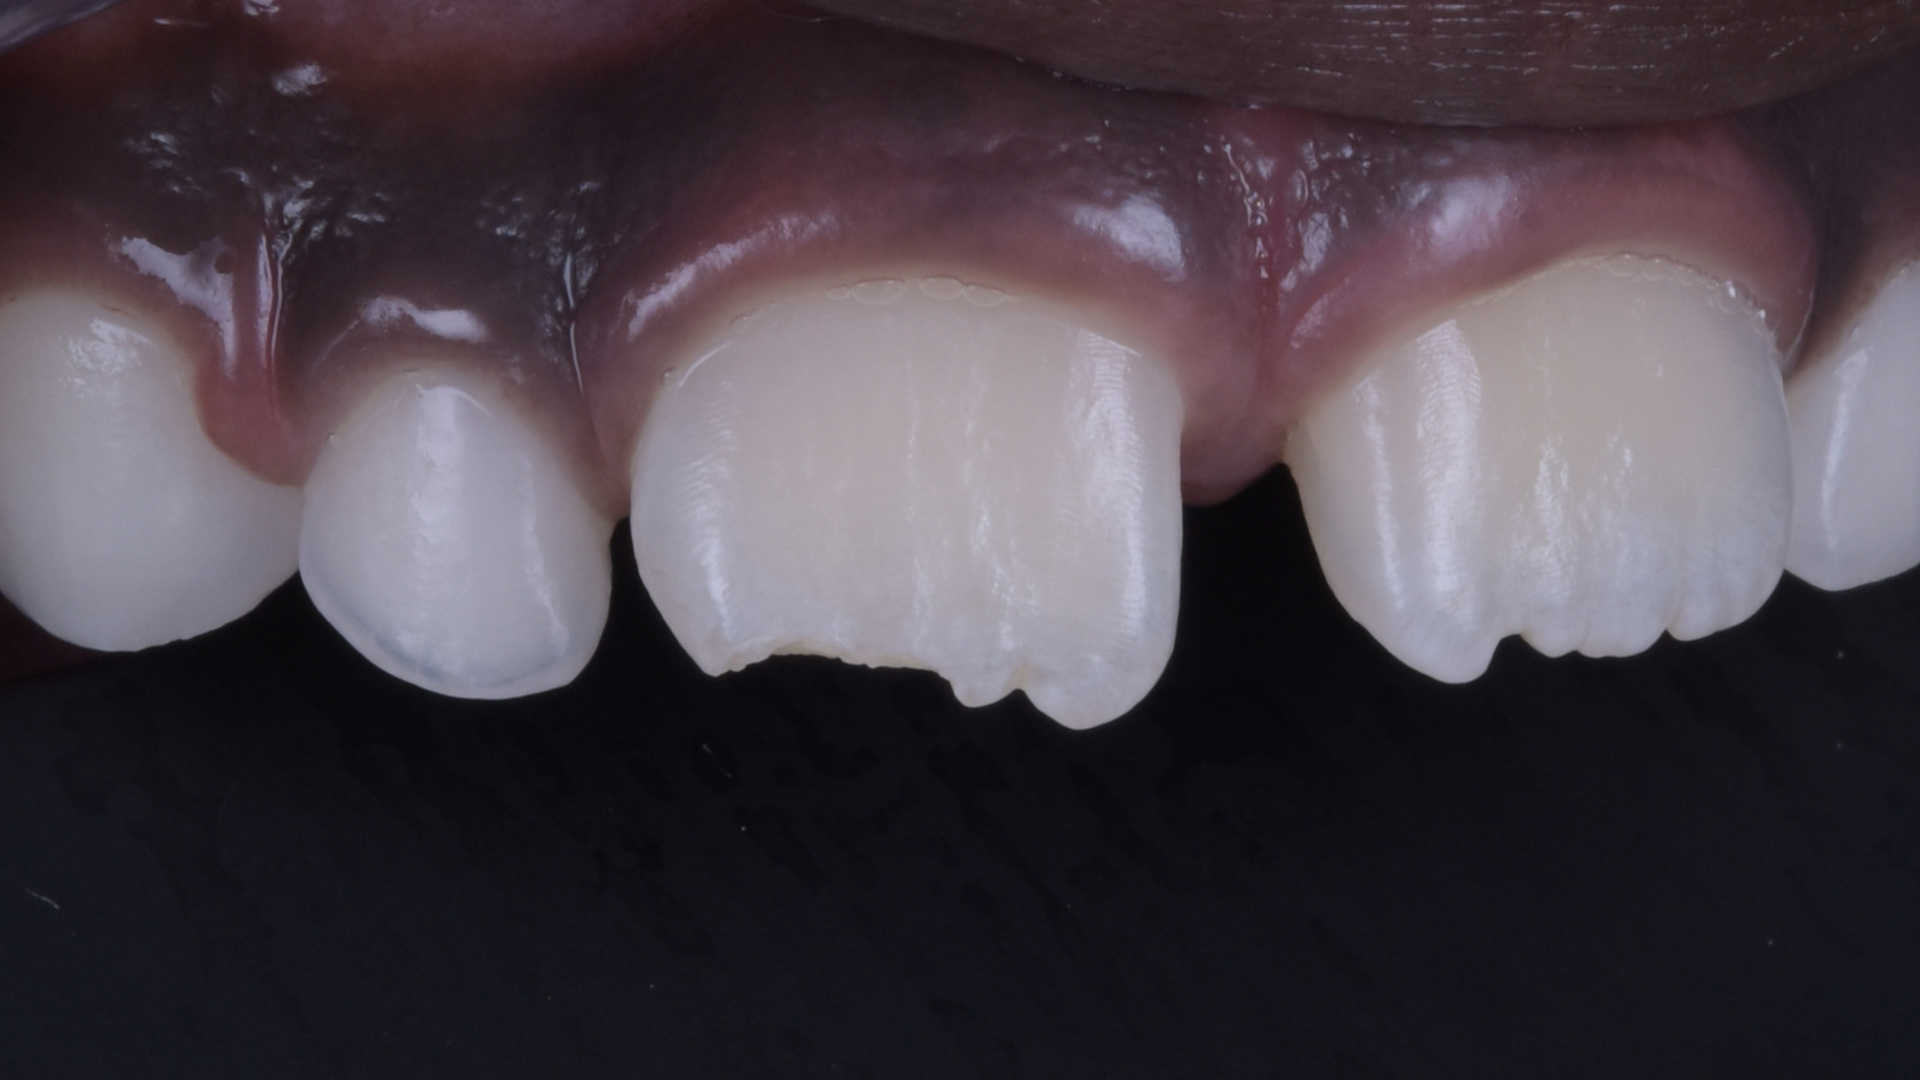

Ausgangssituation

Detailansicht der Oberkiefer-Frontzähne. Horizontale Kronenfraktur unter Einbeziehung der Inzisalkante sowie des distalen Anteils von Zahn 11.

Detailansicht des frakturierten Zahnes.